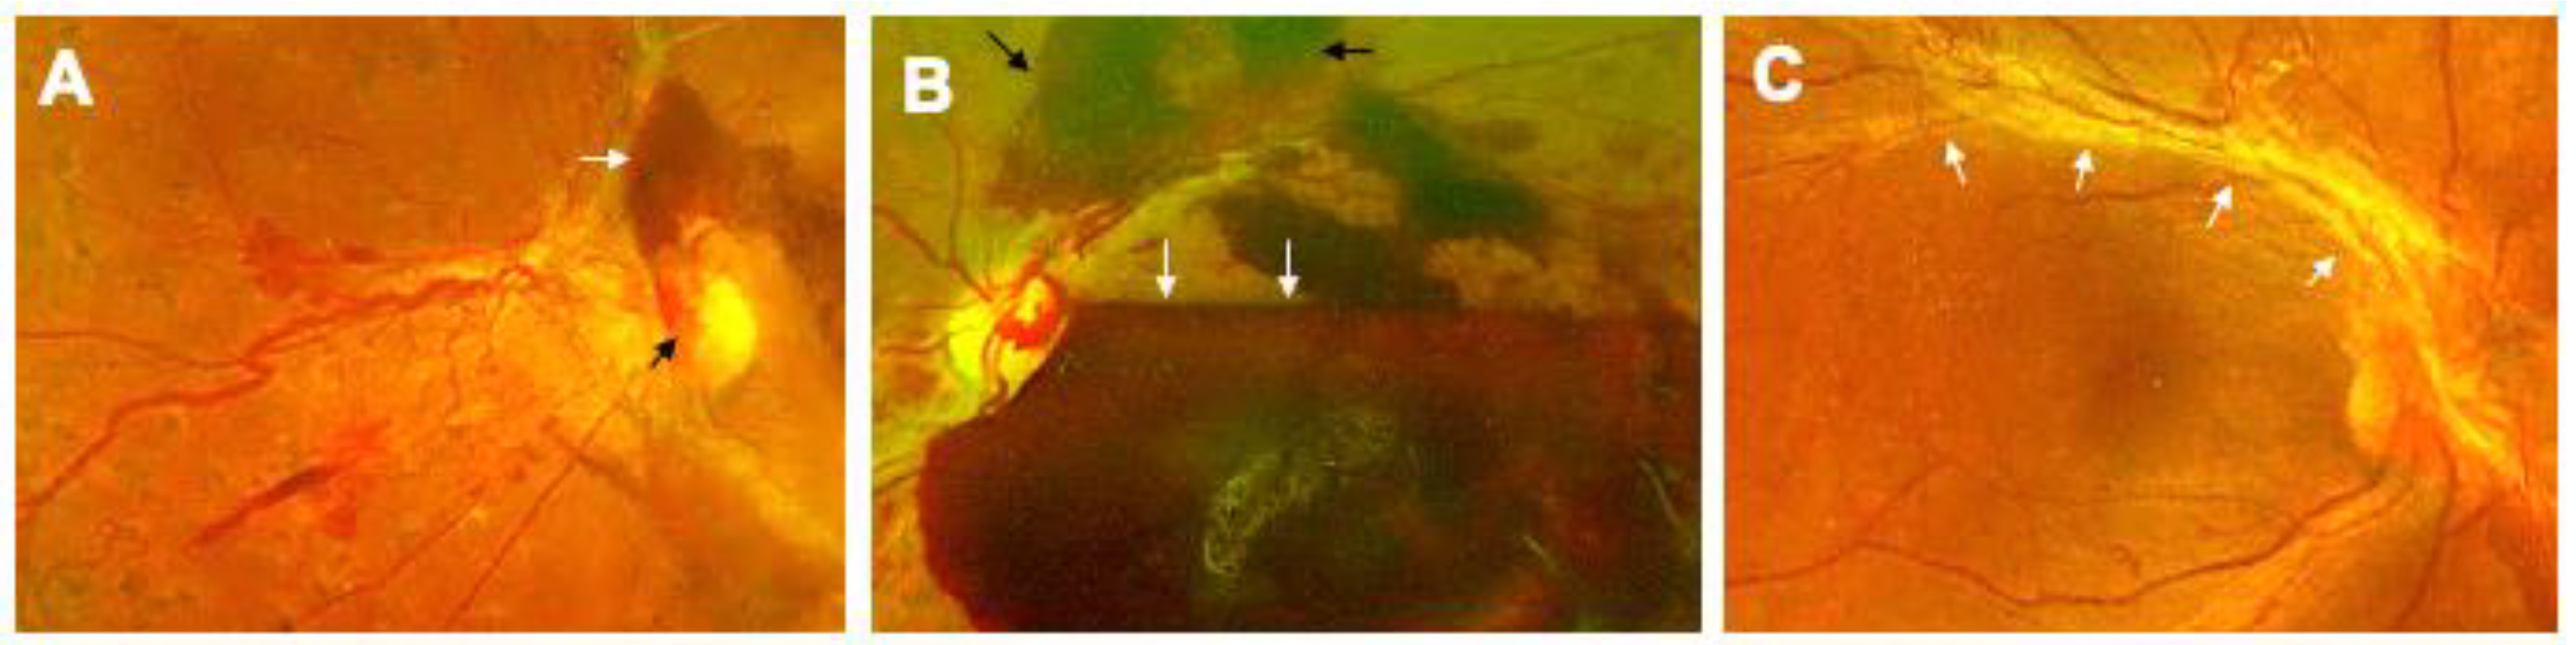

3.2. Proliferative Diabetic Retinopathy (PDR)

3.3. Diabetic Macular Edema (DME)